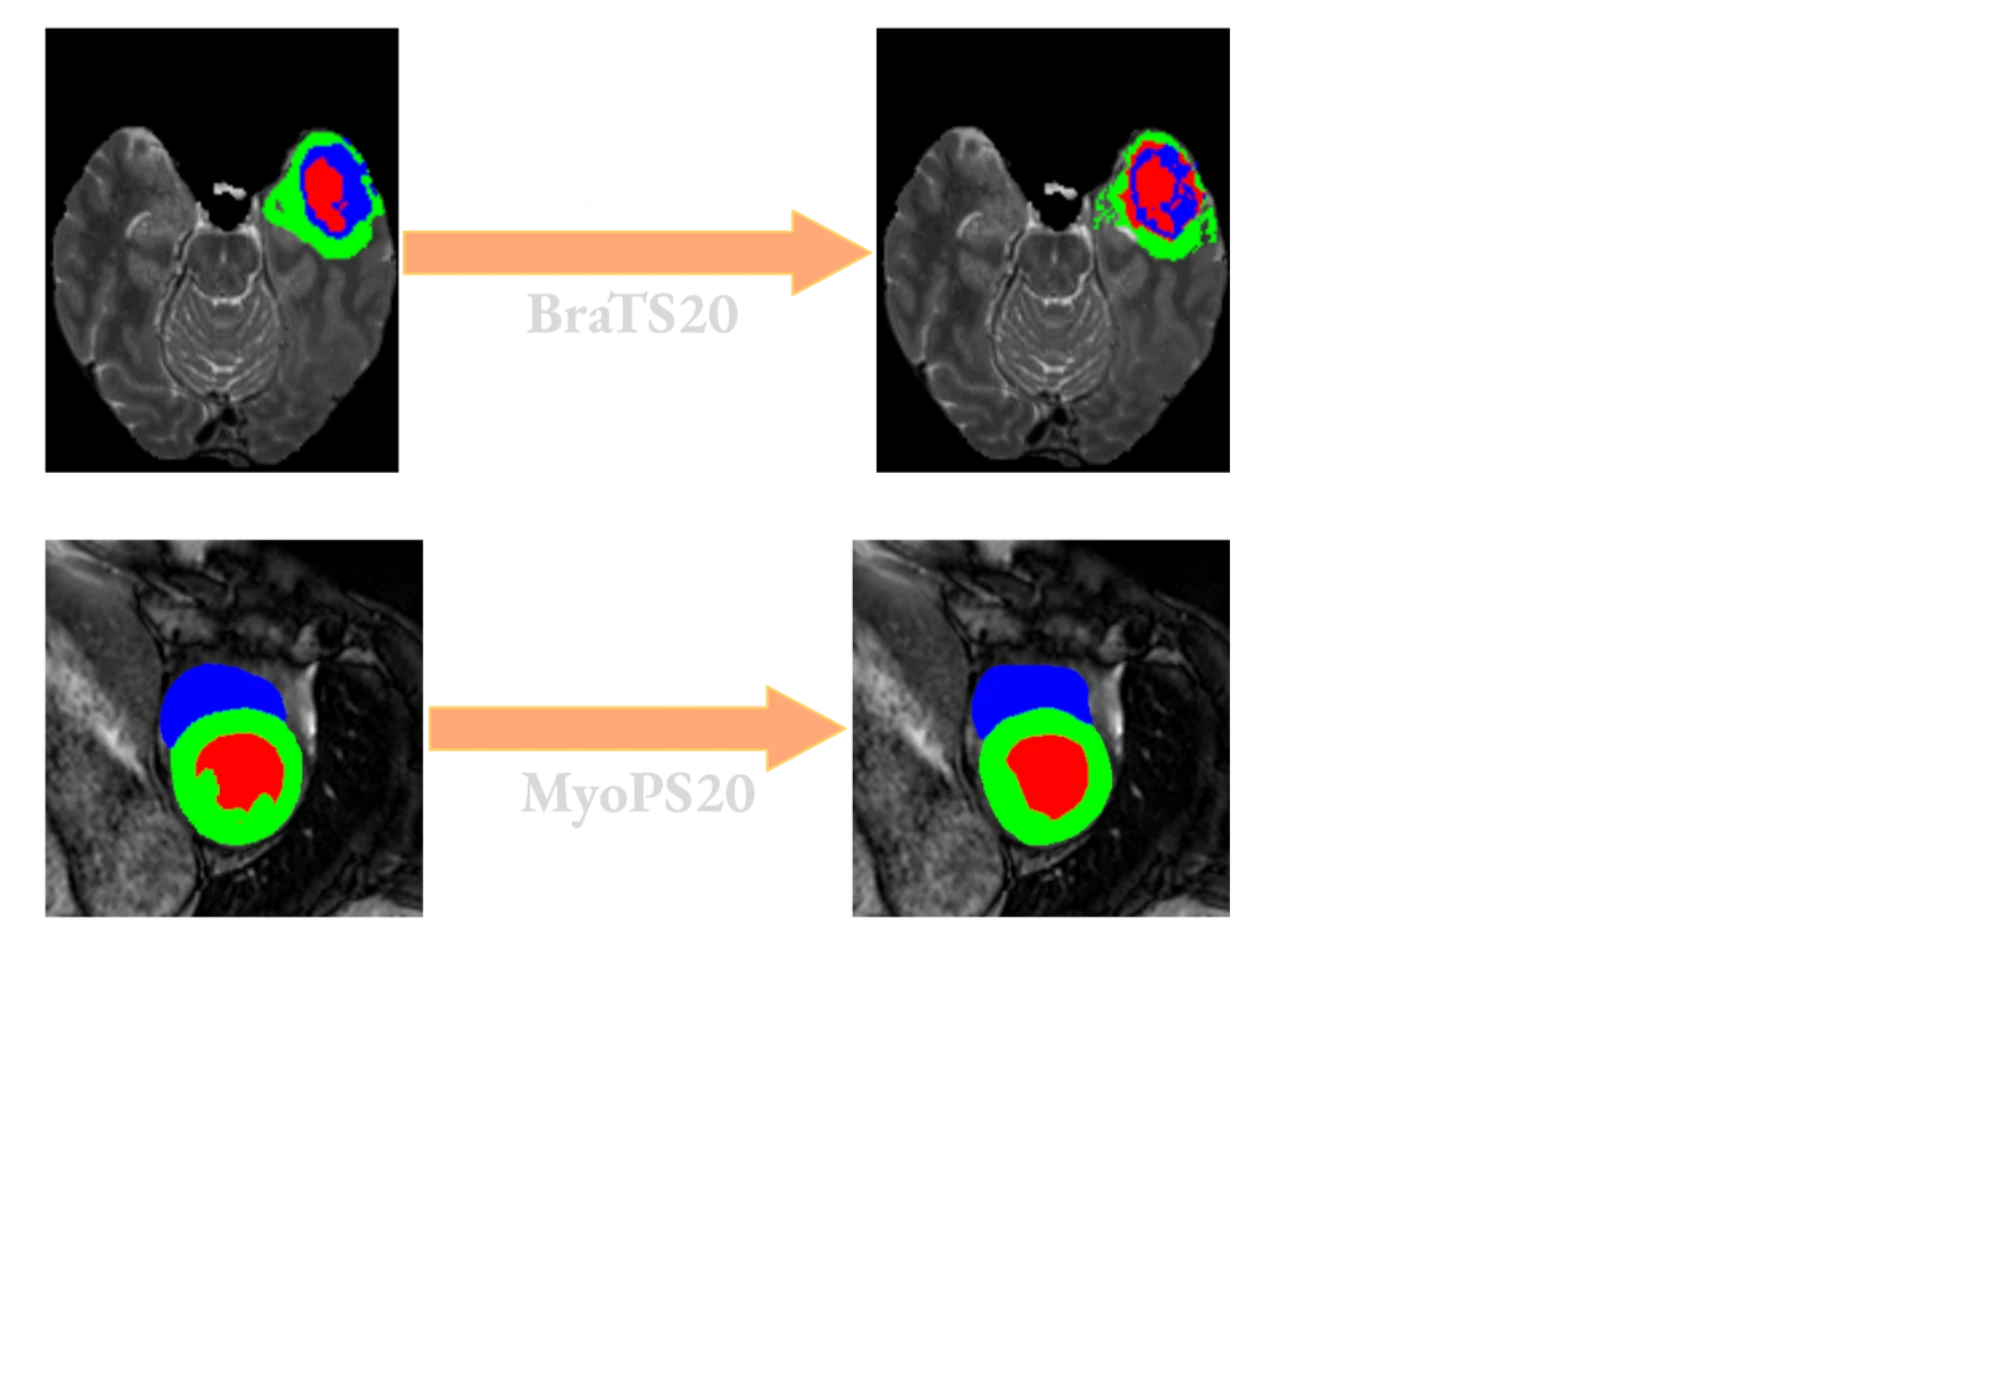

Quantitative Auswertung, qualitative Beispiele und Gegenüberstellung mit verwandten Arbeiten.